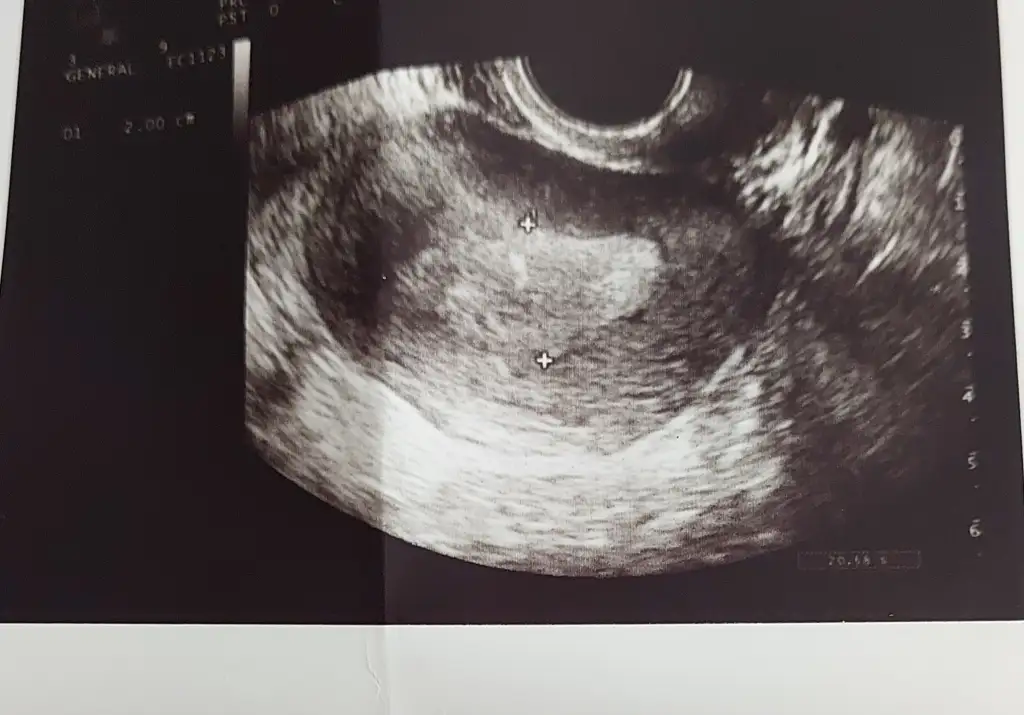

5 haftalık hamileyim kese şekline göre cinsiyet yorumlayabilirmisinz

Kızlar bata 2 gün var siz bir şey görebiliyor musunuz 🥹🥹🥹